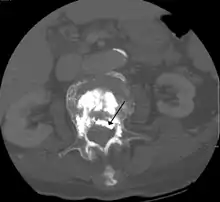

وعادة ما يتم إجراء رأبُ الفقرة على يد جراح العمود الفقري أو أخصائي التدخل الإشعاعي وهو إجراء الحد الأدنى للغزو، وغالبا ما يعود المرضى إلى المنزل في نفس يوم العملية أو اليوم التالي ويتم إعطاء المرضى التخدير الموضعي والتخدير الخفيف في العملية بالرغم من أنه يمكن القيام بها باستخدام مخدر موضعي فقط للمرضى الذين يعانون من مشاكل صحية والمرضى الذين لا يستطيعون تحمل المهدئات بشكل جيد. خلال العملية، يتم حقن ملاط العظام مع خزعة الإبرة في الفقرة المنهارة أو المكسورة، يتم وضع الإبرة مع جهاز الأشعة السينية التوجيهي، ويتصلب الملاط (puma وهوالأكثر شيوعا، بالرغم من وجود الكثير من الملطات الحديثة التي تستخدم جيدا) بسرعة ليشكل الهيكل الداعم داخل الفقرة الذي يوفرالإستقرار والقوة، وتكون الإبرة فجوة في جلد المريض والتي يمكن تغطيتها بسهوله بعد القيام بهذا الاجراء.